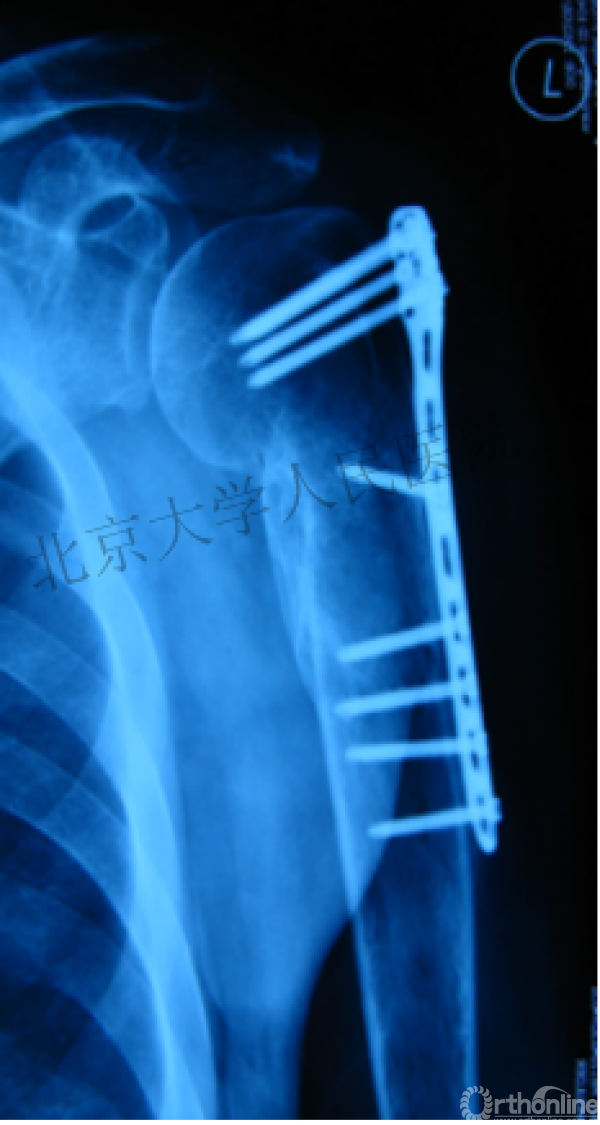

内侧皮质粉碎,低位外科颈骨折,肱骨头-干角维持困难。

术后复位丢失,肱骨头内翻畸形。

能否该偏心固定(钢板)为髓内固定,增加力臂?

早知今日,何必当初?

此时对比髓内钉是不是有很大优势?

另一个留有遗憾的病例,您的选择?PHN?